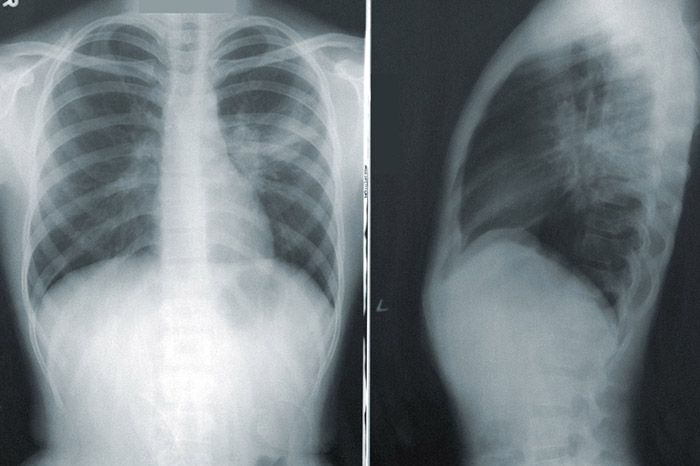

В Петербурге с конца апреля пневмонию диагностировали у более чем 17 тысяч человек

В Петербурге с 26 апреля по 8 июля диагностировали более 17 тысяч пневмоний. Это следует из данных сортировочного COVID-центра Медицинского института им. Березина Сергея (МИБС).

В самом МИБС за этот период выявили 10 053 пневмонии. Еще 7149 пневмоний обнаружили у пациентов в других центрах компьютерной томографии.

Сортировочный центр МИБС — это первый амбулаторный сортировочный центр компьютерной томографии для диагностики пациентов с ОРВИ, внебольничной пневмонией и подозрением на коронавирус в Петербурге. Он начал работу 26 апреля. Центр используется для диагностики пневмонии у пациентов с подозрением на коронавирус и их распределения по стационарам.